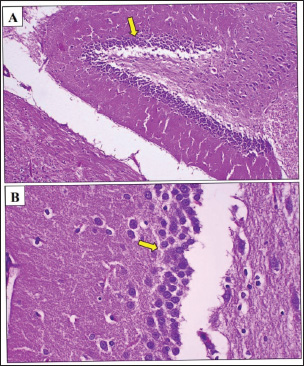

In contrast, the positive control group, which only received AlCl3 treatment, exhibited pronounced histopathological changes. There was a significant reduction in the number of granule cells compared to the negative control group (Fig. 2A,B), along with clear signs of neuronal loss and degeneration in the dentate gyrus of the hippocampus. This was evidenced by cytoplasmic vacuolization and gaps, indicating neuronal damage. Furthermore, a statistically significant (p < 0.05) increase in amyloid beta protein aggregation was observed in this group, as shown in Table 1.

Fig. 1. Photomicrograph of the hippocampus of rat treated with Arabic Gum. (A, B) Neurodegeneration (black arrow) was observed in the dentate gyrus stratum granulosum cells within the affected hippocampus, characterized by the presence of cytoplasmic vacuoles in granule cells. Additionally, the density of granule cells (yellow arrow) was lower in the negative control group than in the positive control group, likely due to neuronal loss in the dentate gyrus. However, the number of granule cells was higher in the positive control group than in the positive control group. In addition, mild neurodegeneration (blue arrow) was observed in neurocyte of Cornu Ammonis region 3. H&E. A: 100x and B: 400x.

The Gum Arabic-treated group demonstrated notable improvement relative to the positive control group. Histological analysis (Fig. 3A,B) revealed less severe neurodegeneration, with a higher number of granule cells, suggesting a partial neuroprotective effect. Amyloid beta accumulation was reduced by approximately 50% in the Cornu Ammonis region compared with that in the negative control group (Fig. 4). Statistical analysis confirmed a significant (p < 0.05) increase in cell preservation in the Gum Arabic group compared with the Fenchol and memantine groups. In the Fenchol-treated group, histological assessment showed reduced granule cell density compared with the negative control, but with minimal amyloid beta deposition, particularly in the hippocampus, where plaques were nearly absent (Fig. 5A,B). The histogram in Figure 6 demonstrated a statistically significant (p < 0.05) protective effect in this group compared with both the Gum Arabic and memantine groups.